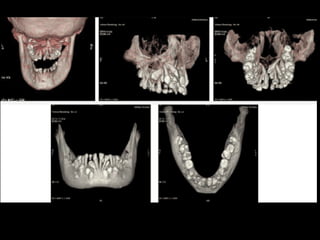

Panoramic (reconstructed from CT)

The most likely diagnosis for the facial asymmetry of this young girl is an

undiagnosed condylar fracture that most likely happen when she falled on a meta

crossbar bar ladder 2 or 3 years ago while she was 4 - 5 years old or so. The

condylar stump has healed and a new condylar head has formed, but the losted

substance of the condyle is gone. Therfore, the height of the ramus has

shortened.

The left ramus and condylar neck are shorter and the left eminence has no slope

if any. Healing and normal growth had reshaped both condyle and eminence.

!

Read more

When looking to the condyle from an anterior view, one can see the oblong

shape of a condyle but the left condyle is smaller.

The midline are not coincident. Note that the lower midline is toward right like

the occlusal plane canting to the right. This can be explained by the lack of

heigh of the left ramus and as normal growth occur, there is a wagon wheel

effect and the midline deviate toward the normal side, the occlusal plane is

moving up on the affected side.